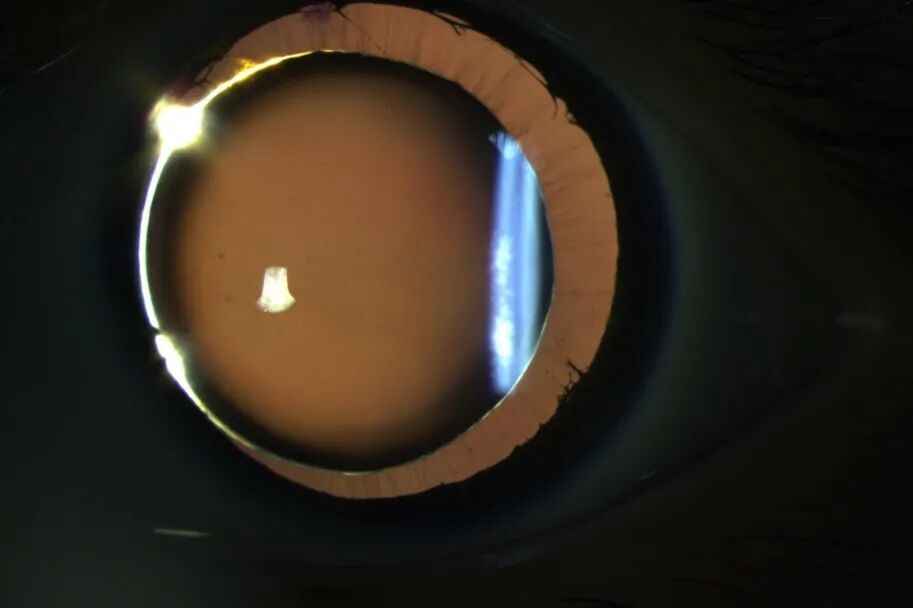

小章术后眼球情况

小章术后:

视力:双眼达到5.0

前房深度正常、眼压正常